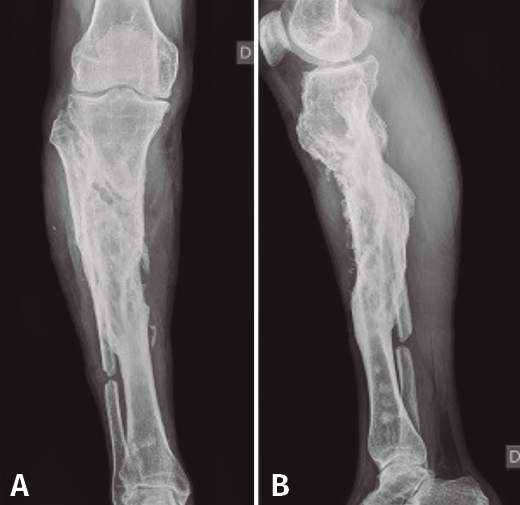

En el estudio radiológico (Figura 2) se objetiva fractura consolidada de la tibia con amplia desestructuración ósea.

Figura 2. Radiografías de frente y de perfil de tibia-peroné donde se objetiva fractura consolidada con amplia desestructuración ósea.